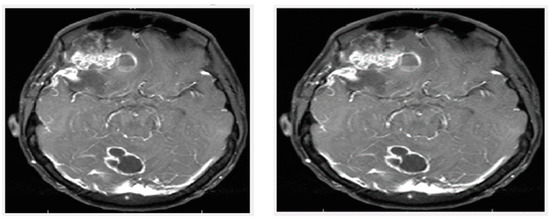

The recursive operation is completed when IE would be less than the equivalent for tolerance Tie. For this proposed approach, the test image is in Figure 6, which indicates the results.

Figure 6.

(Left): original image; (right): filtered image.